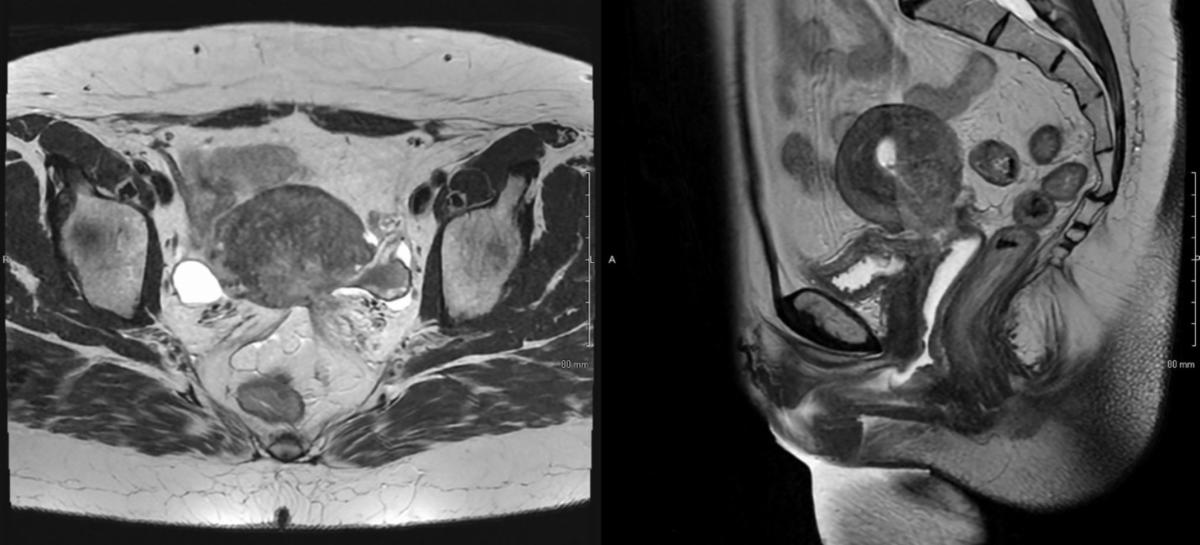

A 38-year-old woman with 1 year history of menometrorrhagia and prior abnormal Pap was found to have FIGO stage IIB moderately-differentiated, HPV-associated, cervical squamous cell carcinoma. Her disease had extensive involvement of the myometrium, parametria, and vagina without nodal involvement (Figures 1A-B). On speculum exam, the cervix was flush with the upper vagina and replaced by friable, irregular, tissue with a visible os. Bimanual exam demonstrated a 5 cm cervical mass with extension to the anterior and left vaginal fornices, and left parametrial extension on rectovaginal exam.

Given the extent of disease, she was recommended and ultimately treated with definitive external-beam radiotherapy (EBRT) and concurrent weekly cisplatin (40 mg/m2 IV) followed by four fractions of high-dose-rate (HDR) cervical brachytherapy. EBRT was delivered to the pelvis and at regional nodes to 45 Gy, followed by HDR brachytherapy, 4 fractions of 7 Gy each to the cervical high-risk clinical tumor volume (HR-CTV), delivered twice-weekly. Serial exams during EBRT showed early response. Repeat pelvic MRI in week 4 confirmed tumor response but with residual disease (Figure 2).

Figure 1B – pre-treatment Pelvic MRI, T2 sequence

Figure 2 – mid-treatment Pelvic MRI, T2 sequence